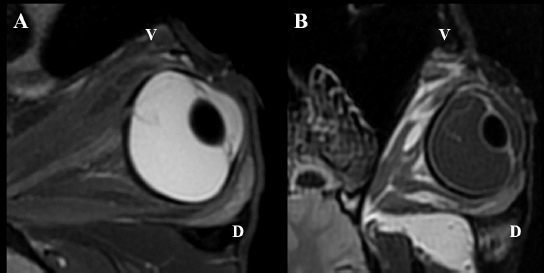

Intraocular lesions found on US and MRI of both horses were consistent with the ophthalmic examination. Complete RD OS and hyperechoic vitreous floaters OU were noted on US (Fig. 4). RD was also evident OS on MRI, more conspicuously on T2W and FLAIR sequences. In T2 sequences, the detached retina was identified as a V-shaped membrane of intermediate signal inside the hyperintense vitreous and reaching the optic disk (Fig. 5A), while it was slightly hyperintense in comparison to the hypointense vitreous chamber on FLAIR acquisitions (Fig. 5B). There was a subjectively abnormal positioned optic disk OU on US and MRI, suggesting ectopic ONH. OS was flattened at the level of the ONH in both horses. Except for a subarachnoid emphysema due to postmortem changes, the brain looked otherwise normal on MRI. Based on US, the axial globe length measured 39.2 mm OS and 41.5 mm OD of case 1 and 45 mm OU in case 2.

Fig. 5. MRI OS, case 2. T2W oblique plane image highlighting the hypointense-detached retina reaching the optic disk and in direct continuity with the optic nerve. Note the hyperintense periphery of the optic nerve, corresponding to the normal thin layer of cerebrospinal fluid surrounding it (A). FLAIR frontal plane image showing the difference of signal between the slightly hyperintense retina within the hypointense vitreous chamber (B). D: dorsal; V: ventral.